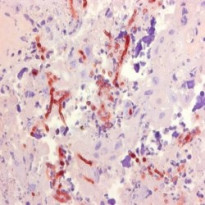

| 产品描述 | Mouse Monoclonal antibody [WF-AF-1] recognizes Aspergillus SPP This antibody recognizes wall fraction (WF) of Aspergillus fumigatus. This antibody specifically recognises members of the Aspergillus spp. including A. flavus and A. niger, reacting strongly with walls and septae, and to a lesser extent within the cytoplasm of hyphae. A. fumigatus, a thermophilic, opportunistic and angio-invasive filamentous fungus, is the main causative agent of systemic Bovine aspergillosis, a worldwide and often fatal respiratory disease of cattle. Clone WF-AF-1 has been successfully used in immunohistochemistry for the specific and consistent in situ diagnosis of Bovine systemic aspergillosis, attributed to its binding to the major cell wall component, galactomannan. Clone WF-AF-1 has also been used for the identification of aspergillosis in Human tissue sections. Clone WF-AF-1 does not bind to water-soluble somatic antigens (WSSA) of Aspergillus spp., but may react with galactomannans of members of the genus Penicillium. |